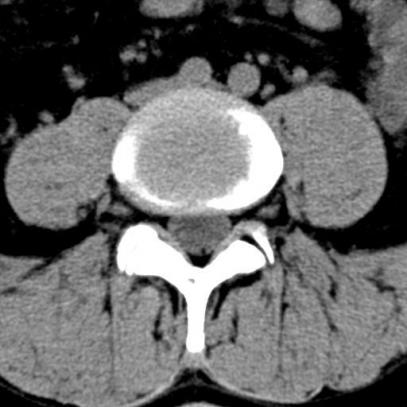

Similar to the cervical spine it is enough to initiate an X- ray or a nuclear resonance imaging. If the patient suffers from slipped vertebral bodies or a multiple stenosis it is most helpful to perform a myelographic imaging to get the best impression.